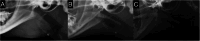

Feline nasopharyngeal stenosis (NPS), characterized by narrowing of the nasopharyngeal passage, results in chronic stertor and increased inspiratory effort. While rhinoscopy is the definitive diagnostic modality for NPS, the utility of nasopharyngeal radiography in diagnosis remains under-documented. The purpose of this study is to evaluate the diagnostic accuracy and describe the characteristic radiographic findings in cats with NPS by comparing radiographic findings in cats with stertor but without stenosis. This is a multicenter, retrospective, cross-sectional study. Fifty-two cats with stertor who underwent both rhinoscopy and lateral nasopharyngeal radiography were included. They were divided into two groups: those with NPS (n = 21) and those with stertor without stenosis (ND group, n = 31). Radiographs were reviewed by two board-certified radiologists to determine the presence, location, and morphology (broad or membranous) of NPS, as well as the morphology of the soft palate and the presence of oropharyngeal gas. Radiographic evaluation demonstrated a high diagnostic accuracy for NPS with a sensitivity of 100%, specificity of 83.9%, and overall accuracy of 90.4%. The radiographic morphology of the NPS was broad in 18 cats and membranous in 3 cats. A "bent" soft palate was observed only in the NPS group (19%, n = 4). The presence of oropharyngeal gas was similar in both groups (57.1 vs. 58.1%). However, because radiographic diagnoses were made by consensus between two radiologists, the reported accuracy may be overestimated. Given its high sensitivity, nasopharyngeal radiography serves as an effective initial screening tool for NPS, likely streamlining the diagnostic pathway in cats with stertor.